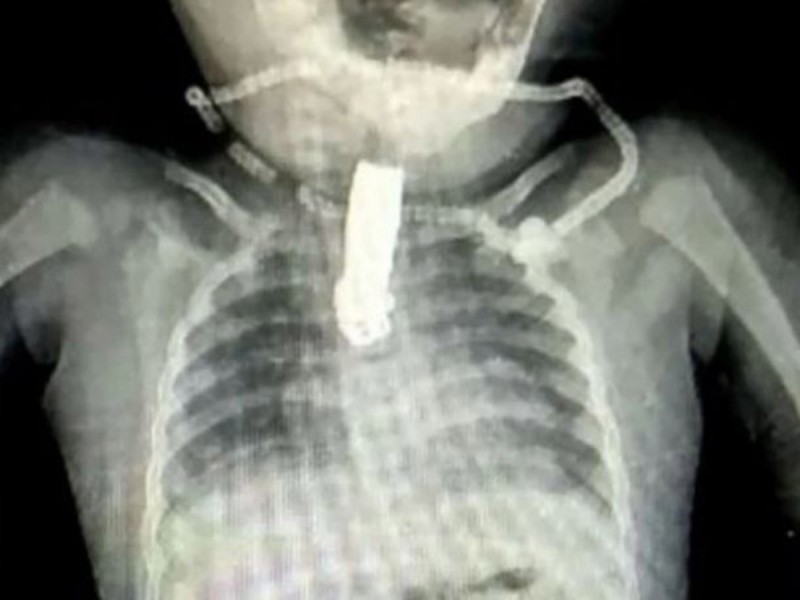

Una radiografía muestra el objeto atorado en la garganta de la bebé, los médicos estudiaron muchas posibilidades para retirar el objeto atorado en la garganta.